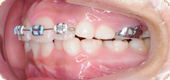

矯正治療の装置には、以下のような種類があります。

治療目的や歯の状態、生活環境によって治療法が異なります。